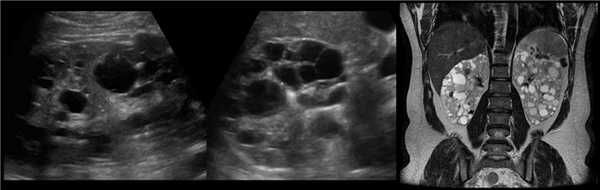

Рисунок. У новорожденного на УЗИ почек определяется гидронефроз (1) и расширенный мочеточник (2) справа. В мочевом пузыре двустороннее уретероцеле (3). При исследовании левой почки структурных изменений не выявлено.

Рисунок. На УЗИ определяется удвоенная чашечно-лоханочная система, расширена лоханка верхнего сегмента (1) и мочеточник на всем протяжение (2, 3), в мочевом пузыре уретроцеле (4). Полное или неполное удвоение чашечно-лоханочной системы возможно увидеть с помощью КТ-урографии.

Рисунок. На УЗИ (1, 2) и КТ (2) множественные кисты в обеих почках. Это аутосомно-доминантный поликистоз почек.